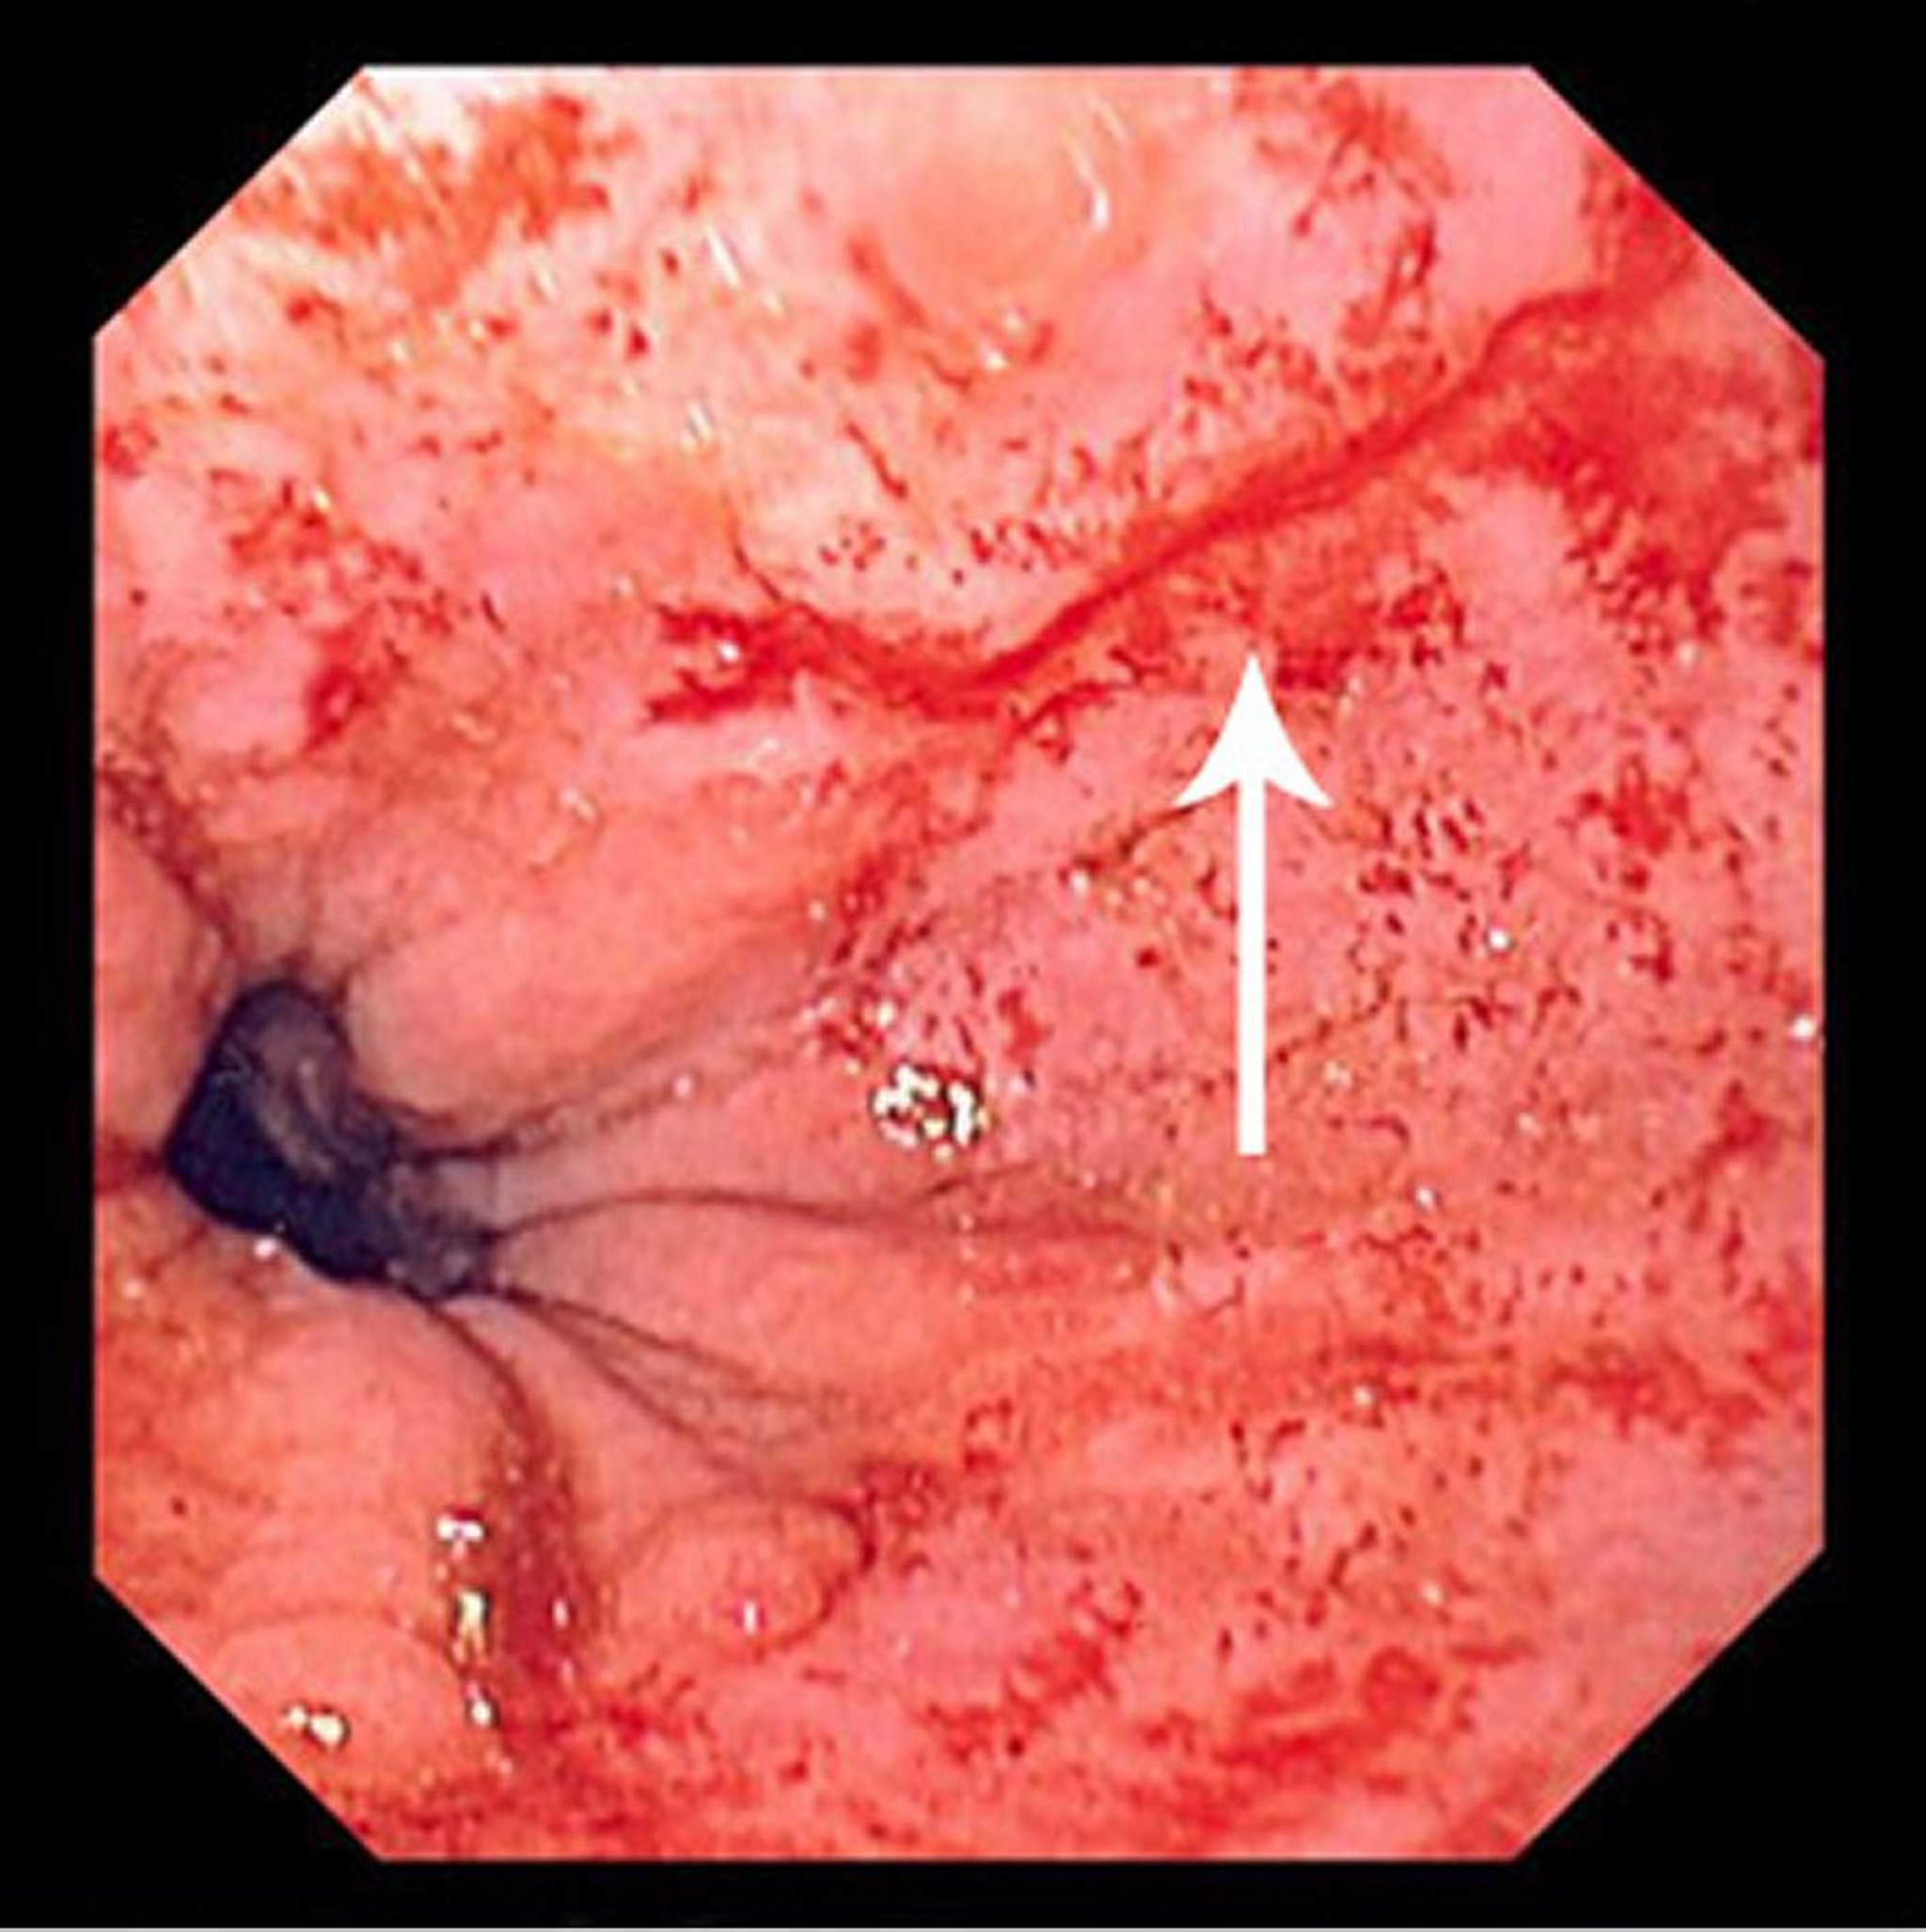

Vết rách Mallory-Weiss

Hình ảnh này cho thấy một vết rách mỏng, thẳng (mũi tên) bắt đầu ngay phía trên đường chuyển tiếp và lan về phía đầu gần.

Hình ảnh do bác sĩ David M. Martin cung cấp.